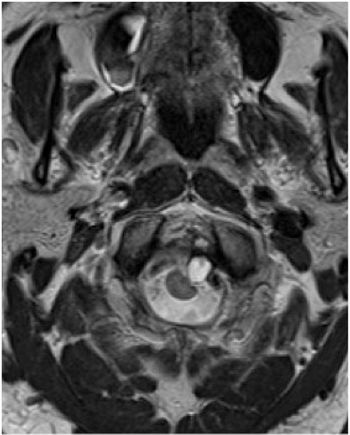

52-year-old female with vertigo, headache, tinnitus, eye twitching, and general instability while walking.